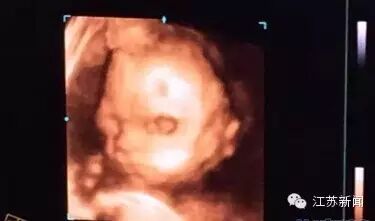

钟雯为什么这么决绝地要保孩子?钟雯说,她自己年纪大了,化疗后还要恢复很长一段时间,加上自身还有缺陷,今后再想要孩子就难了,甚至可能再也怀不上!钟雯说,这个宝宝来之不易,也已经通过四维看到宝宝的模样了,实在舍不得把宝宝拿掉。

钟雯说,其实她早就给孩子起了小名,叫“小朵”,她无法接受失去小朵!原来,在做完了大排畸时,孩子一切正常,她和丈夫通过四维彩超,看到了孩子的样子,孩子笑嘻嘻的样子就像一朵美丽的花!并且她和丈夫都很喜欢绘本《爸爸的木朵》里的小木朵,于是就叫宝宝“小朵”。